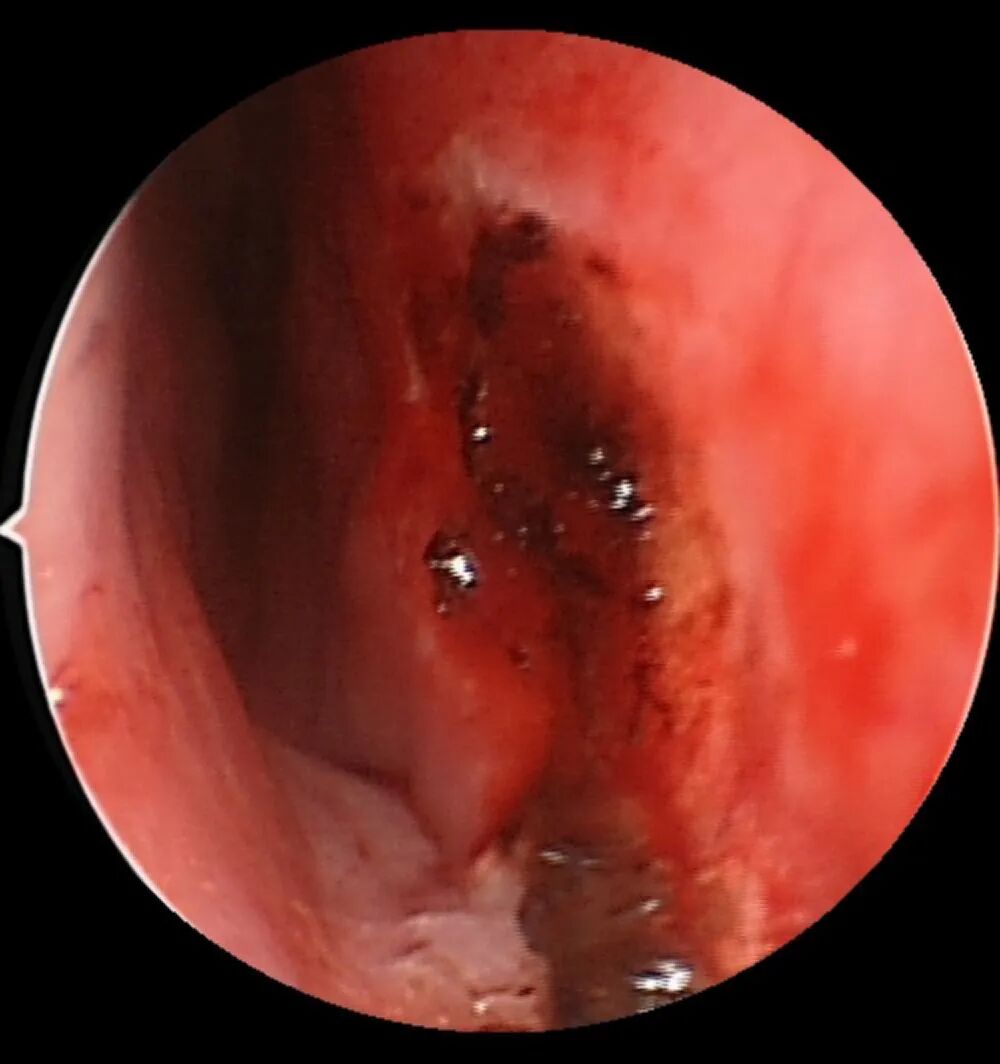

图:粘膜血痂形成,止血

3. 鼻内镜下电凝止血后,鼻腔会形成痂皮,大部分会有鼻痒、喷嚏的症状,避免用力擤鼻引起痂皮脱落出血一般建议止血治疗后进行口服药物控制,局部还可以涂抹药膏控制局部炎症,可以避免粘膜还没有愈合就脱落导致再次出血的情况。